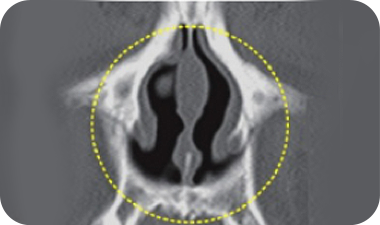

Nasal Valve Stenosis

The nasal valve is the narrowest part of the nasal cavity where air flows inside the nose.

Due to its naturally narrow structure, this area can become even narrower due to various causes, which is known as nasal valve stenosis. When the nasal valve narrows, it can lead to nasal congestion and sleep disorders.

Nasal Valve Stenosis Surgery Expertise

To correct a narrowed nasal valve, a wedge graft technique is used. This involves implanting cartilage between the septum and the side wall to expand the width of the nasal valve.

Before Surgery Narrow Nasal Valve

Cartilage Graft Between the Septum and Side Wall

After Surgery Expanded Nasal Valve Correcting Stenosis